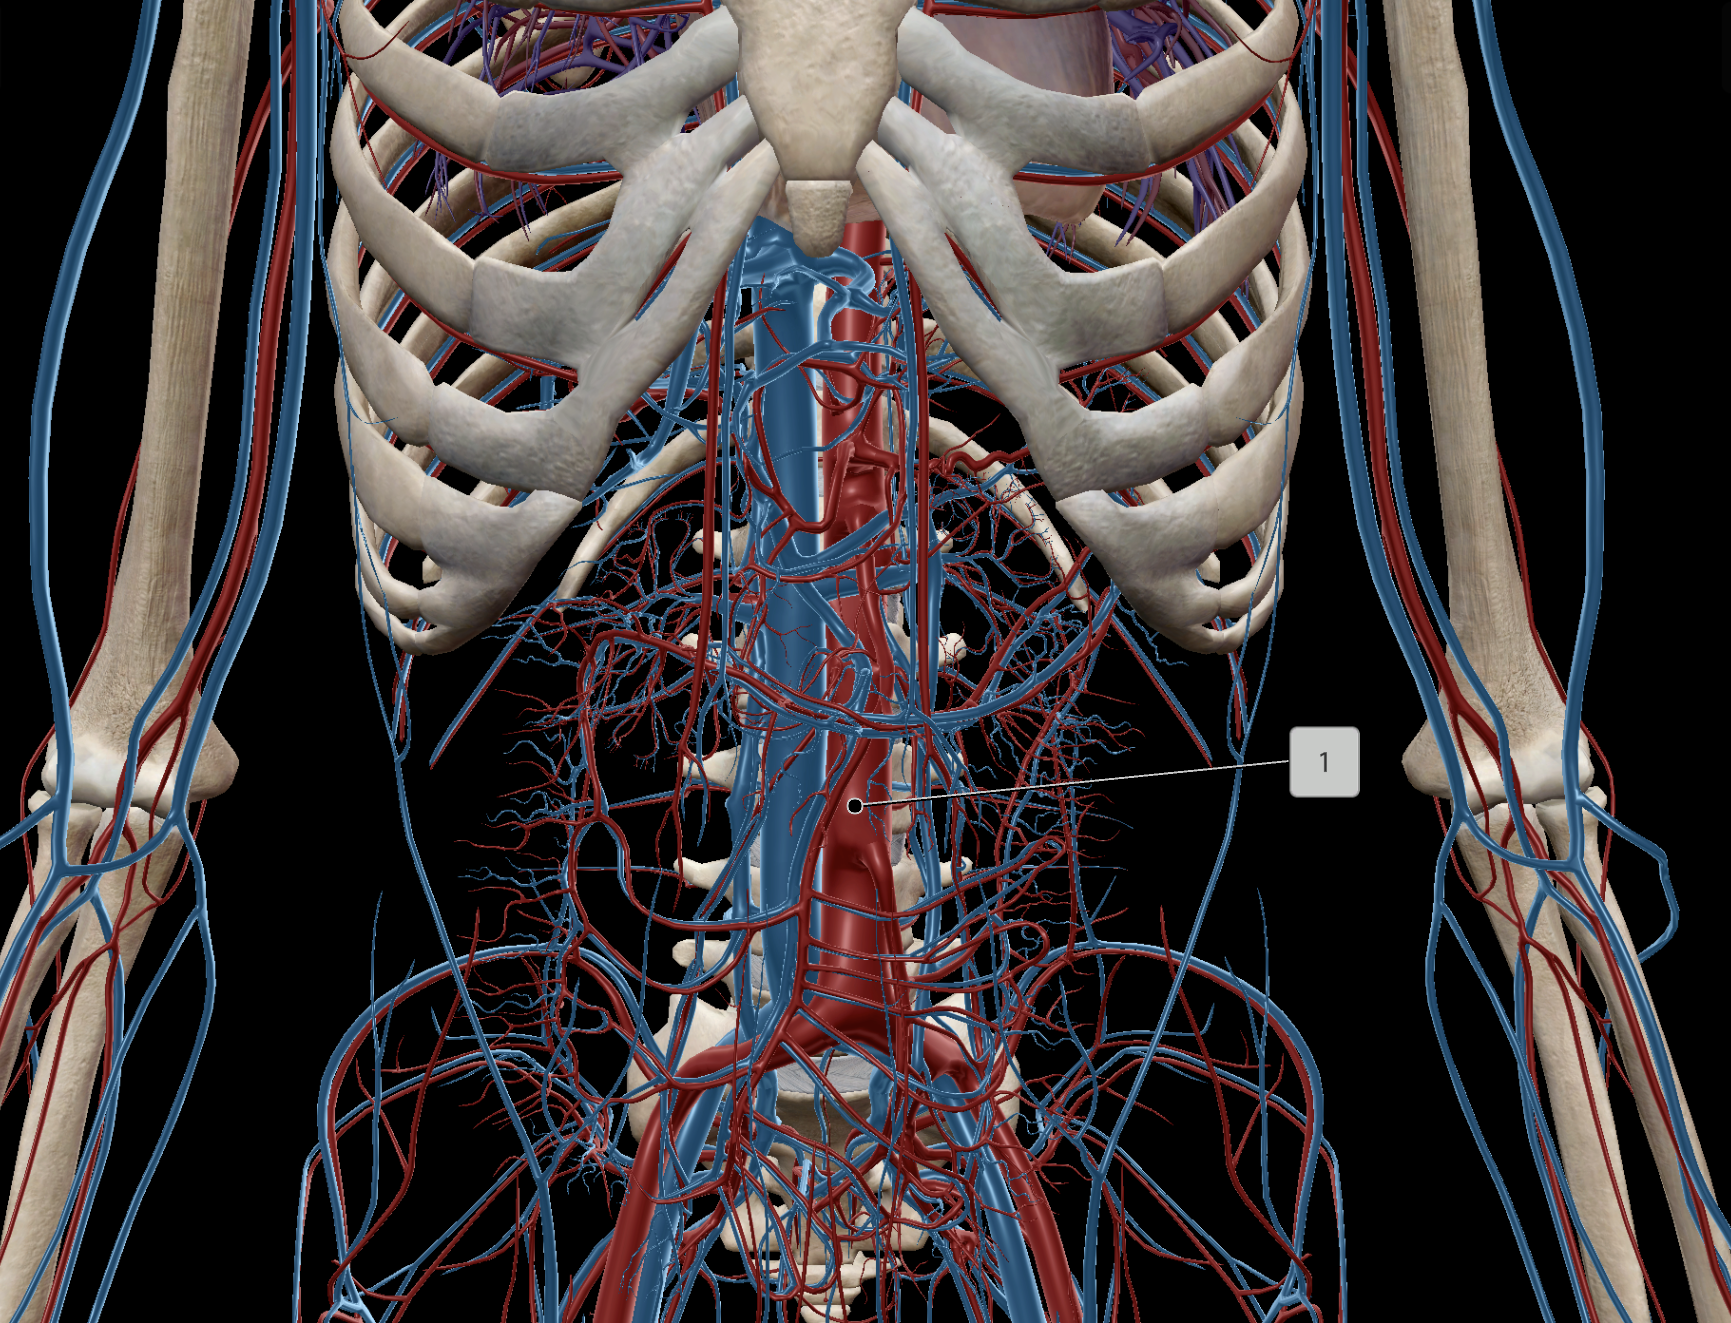

Abdominal Aorta

Inferior Vena Cava

Renal Artery